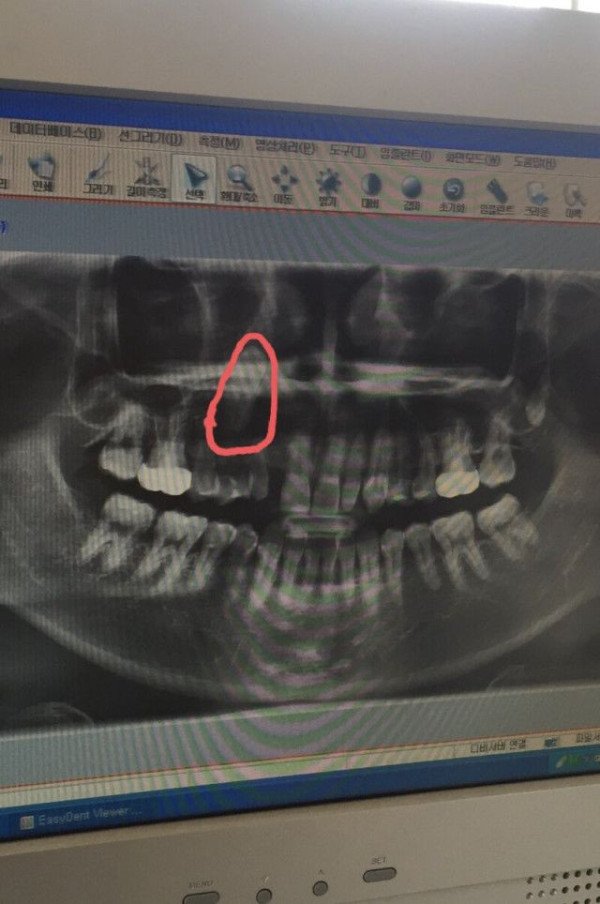

고전 - 루리] 치과의사도 포기한 치아.jpg